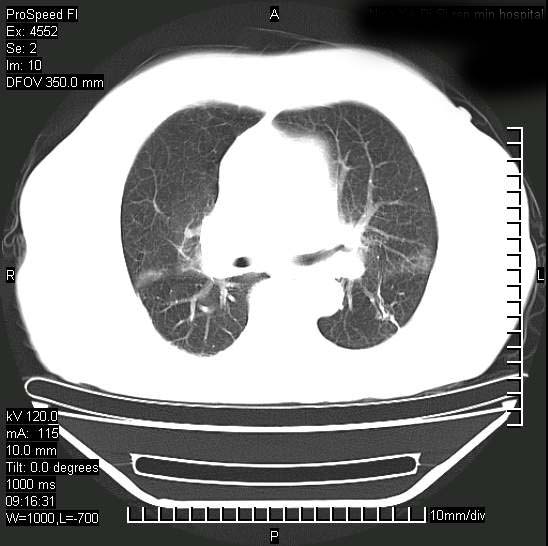

今天ct

短短几天内,病变范围明显增多扩大,以左侧明显,而且双侧出现胸水,还是考虑感染.

无论是肿瘤还是炎症4天的时间都发展够快的,并且还在治疗中,如果说是左肺癌那么右肺的病变不好解释,本人更加倾向于炎症,左肺舌叶支气管被痰栓或血凝块堵塞,造成阻塞性肺炎。

1)两肺结核并感染。2)不排除左肺上叶中央型肺癌并阻塞性肺炎、肺不张可能;建议行纤支镜检查。3)右肺门及纵隔淋巴结肿大。4)双侧胸腔积液。